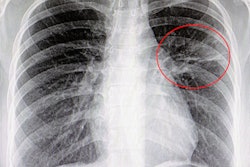

KA Imaging is touting early trial results that show the company's Reveal 35C system with a portable dual-energy subtraction x-ray detector detects more pneumonia cases than traditional x-ray units.

The Reveal 35C technology was shown to detect 25% more pneumonia cases, including COVID-19, than traditional x-rays, according to a paper that was presented at the European Congress of Radiology (ECR) 2021. The trial is ongoing in Toronto, according to the company.